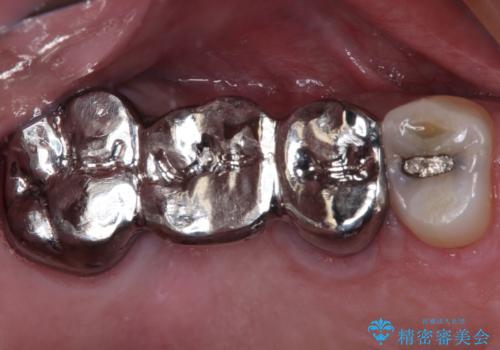

目立つ銀歯をセラミッククラウンに

【セラミッククラウン】詰め物と歯の境目に汚れが溜まる